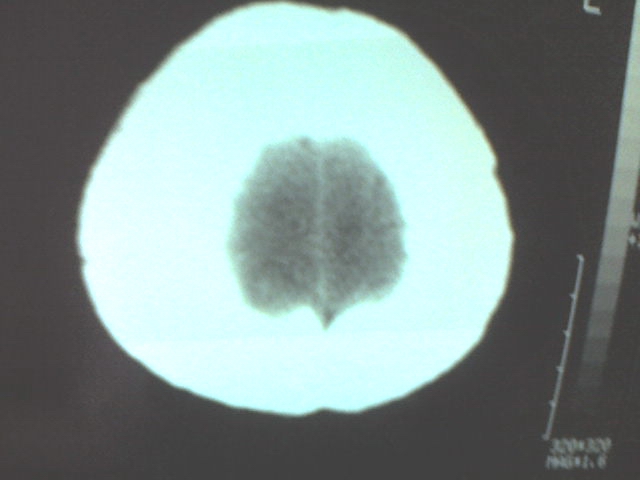

标题: CT12572:女 43岁 头痛恶心呕吐两天请求会诊 [打印本页]

女 43岁 头痛恶心呕吐两天

手机照的,不是太清楚。

右侧大脑镰硬膜下出血

1、右侧大脑镰硬膜下出血2、机器伪影太重,该修修。